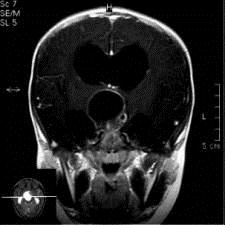

问题 病历摘要:??患者女性,6岁,半年来感觉视力模糊,近10天出现反复头痛,间有恶心呕吐,精神转差,查体:神志清楚,身高90cm,体重25Kg,血压90/55mmHg,右眼视力4.6,左眼视力4.8,双侧视乳头水肿,颈软,伸舌居中,四肢肌张力正常,肌力5级,双侧Babinski征(-)。 入院检查头部MRI,如图所示,诊断有可能是?

选项 A.垂体腺瘤 B.生殖细胞瘤 C.颅咽管瘤 D.视神经胶质瘤 E.蛛网膜囊肿 F.鞍结节脑膜瘤 G.脑积水

答案 CG